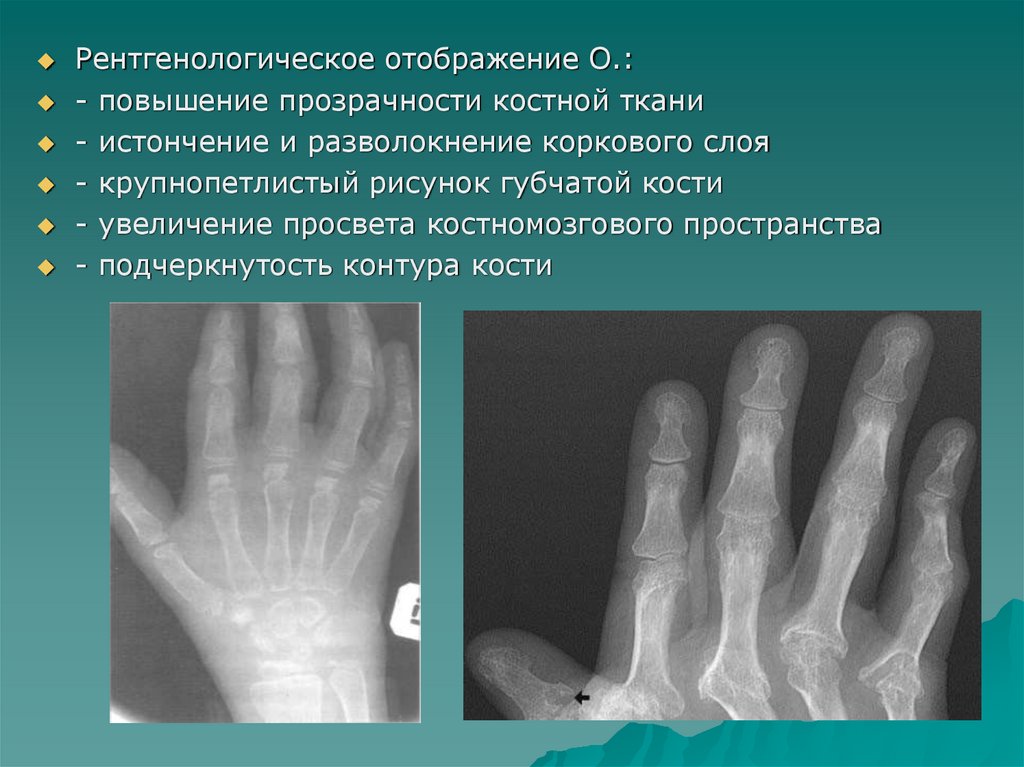

Рентгенологическое отображение О.:

- повышение прозрачности костной ткани

- истончение и разволокнение коркового слоя

- крупнопетлистый рисунок губчатой кости

- увеличение просвета костномозгового пространства

- подчеркнутость контура кости